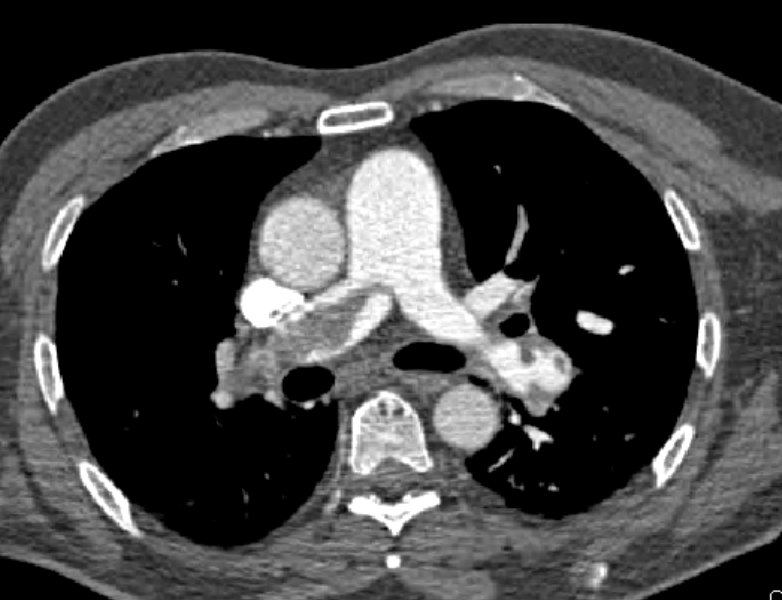

CASE A 64 yo patient is referred to the emergency department(ED) with a persistent tachycardia.…

Pulmonary embolism(PE) and Acute Coronary Syndrome(ACS) causing ischaemia can sometimes be difficult to clinically differentiate.…